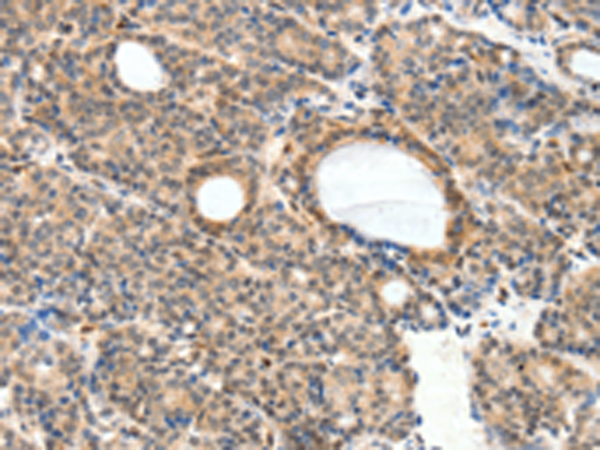

分类: 科研抗体货号: P11178别名: AR; ADR; ALR2; ALDR1应用: WB,IHC反应种属: Human